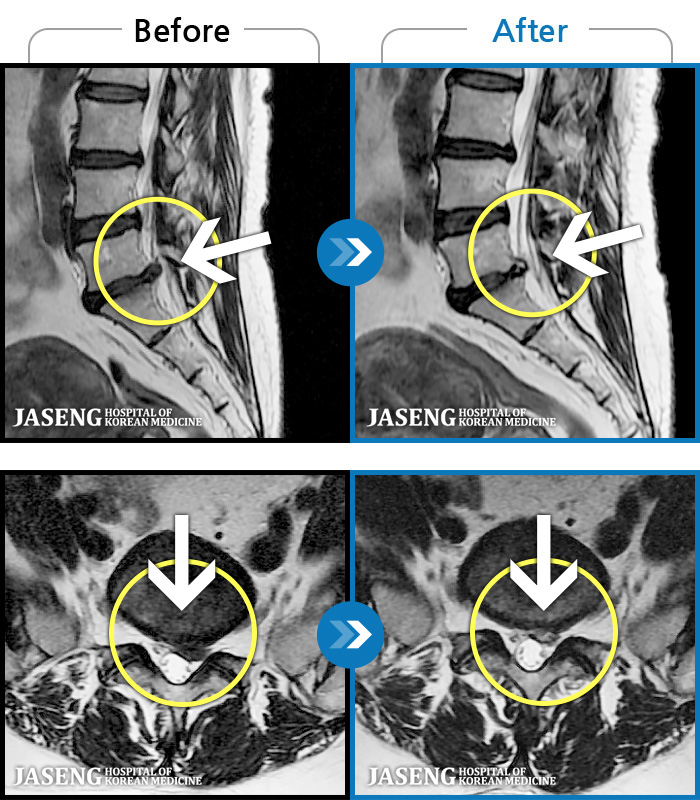

[Ȼ_㸮ũ] 㸮 ְ ٸ ȱⰡ .

No.63

ȸ 154

2025.10.02

[Կñ:23.03.15~25.05.31]

[Ȼ_ũ] īӰ .

No.62

ȸ 326

2025.06.05

[Կñ:23.03.13~24.05.08]

[Ȼ_㸮ũ] 㸮 ϻ .

No.61

ȸ 18,305

2025.05.02

[Կñ:22.01.03~24.07.31]

[Ȼ_㸮ũ] ߸ ҰŸ鼭 ɾ.

No.60

ȸ 614

2024.08.09

[Կñ:18.10.25~24.06.19]

[Ȼ_㸮ũ] ڼ ӵǾ.

No.59

ȸ 688

2024.07.31

[Կñ:22.02.12~23.02.17]

[Ȼ_㸮ũ] 㸮 ٸ ְų Ͽϴ.

No.58

ȸ 615

2023.02.24

[Կñ:18.12.20~23.02.21]

[Ȼ_㸮ũ] 㸮 ٸ ݸ ɾ ɾƾ ߽ϴ.

No.57

ȸ 393

[Կñ:18.11.08~22.07.04]

[Ȼ_㸮ũ] 㸮 ٸ ڷ Ǵ ؽ · ȱ .

No.56

ȸ 182

2022.07.15

[Կñ:21.10.02~22.06.13]

[Ȼ_㸮ũ] 㸮 θ ٸ 㸮 .

No.55

ȸ 171

2022.07.08